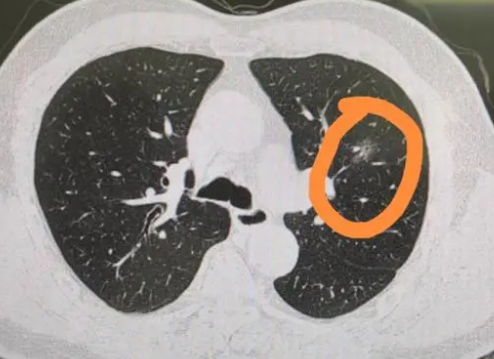

肺部磨玻璃结节,是肺部磨砂玻璃密度一样的圆形、类圆形的云雾状病灶,大小不超过3厘米。根据密度高低,它可以分为纯磨玻璃结节与混合磨玻璃结节。

尽管炎症、结核、真菌感染、肺泡出血等引起肺泡腔充气程度改变的疾病,都可以表现为磨玻璃结节,但长期存在的磨玻璃结节有发展为肺癌的风险,因此需要引起大家的重视。

肺部磨玻璃结节是随访治疗还是手术切除,常常让患者陷入两难抉择。根据我国肺部磨玻璃结节的临床治疗指南,8毫米以下的磨玻璃结节随访即可,若有增大趋势则考虑手术切除。

专家建议:初次发现磨玻璃结节可随访3至6个月,动态复查CT观察结节变化,以最大概率地排除良性感染病变的可能。对于长期存在的磨玻璃结节,需由专业医生辨别分析其病理阶段,以寻找最佳的手术时机。